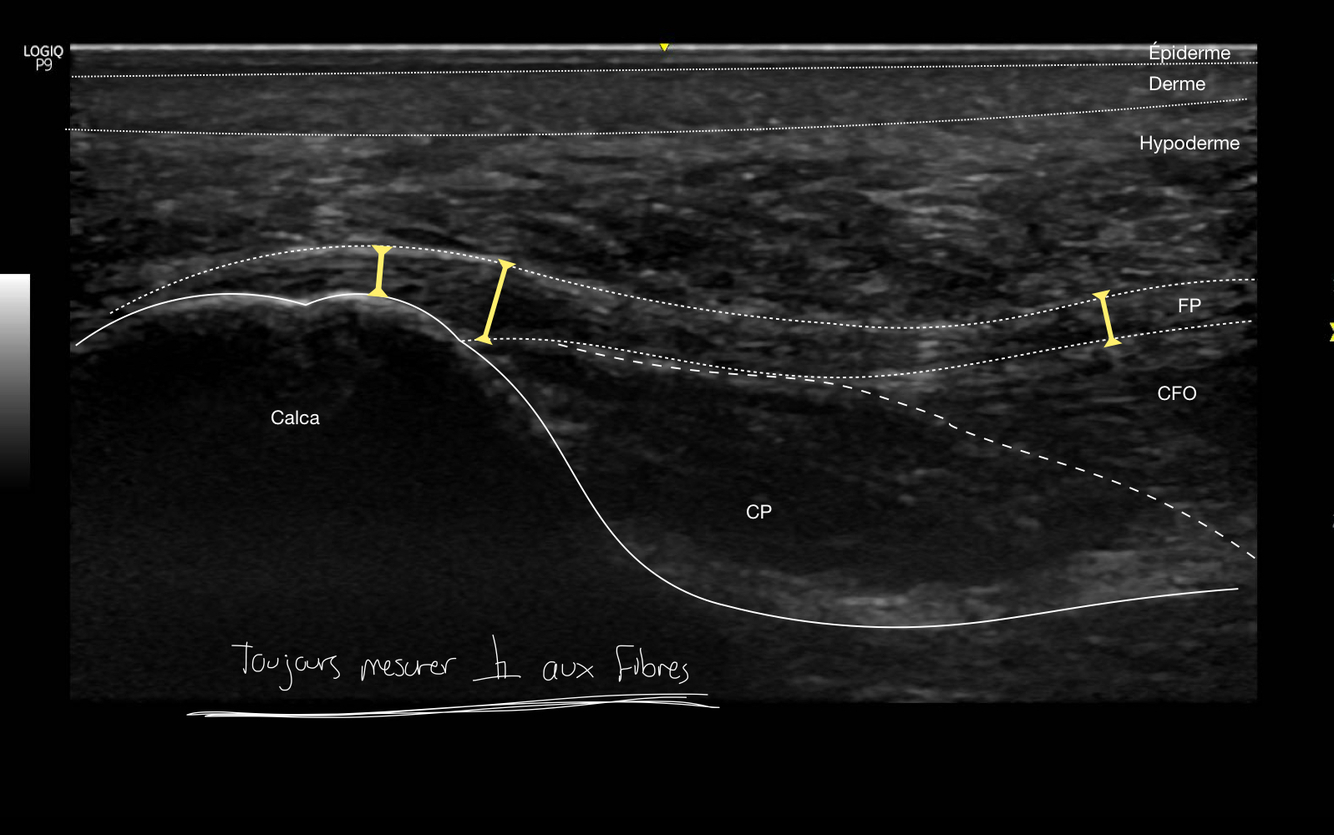

7

Q

Identifie la région du pied analysée ici

A

Il s’agit de la tubérosité médial du calcanéus avec le fascia et les épaisseurs de la peau au dessus